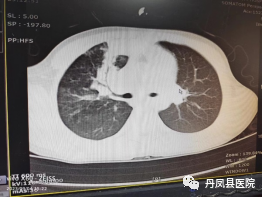

患儿女,9岁11月,因“发热、咳嗽4天”入院,病程中反复发热,热峰39.2℃,伴阵发性连声咳嗽,晨起尤甚,咳黄痰,口服药物无效,来我院,以“支气管肺炎”收住院。入院查体:T36.7℃,P100次/分,R30次/分,BP96/58mmHg。精神可,咽部广泛充血,右肺呼吸音减低,可闻及细小湿性啰音,心音有力,律齐,腹平软,神经系统查体无异常。辅助检查:血常规:WBC 7.00×109/L,L18.80%,M10.10%,N67.40%,RBC4.65×1012/L,HGB128g/L,PLT217×109/L, CRP22.2mg/L;hsCRP>5mg/L。肝功,肾功、血糖、血脂、心肌酶及电解质大致正常;降钙素<0.05ng/ml;支原体IgM抗体:阳性,血沉:23mm/h;凝血常规:D二聚体:2.28ug/ml、余正常;痰培养:阴性;胸部CT:两肺透光均匀,纹理增重,右肺上叶前段、后段见斑片状、团片状高密度实变影影。叶、段支气管开口畅通。入院诊断:支气管肺炎;肺炎支原体感染。诊疗经过及转归:入院后给予阿奇霉素抗感染,低分子肝素钙抗凝,布地奈德,特布他林雾化吸入,孟鲁司特钠口服等对症治疗。治疗11天复查凝血五项正常。复查胸部CT回报:原右肺上叶尖后段大片状高密度影吸收。顺利康复出院。1周后随访患儿无不适。![]()

![]()

治疗前后胸部CT对比病例二